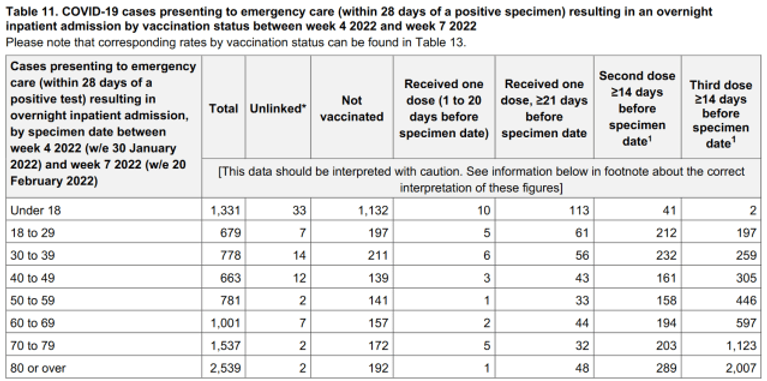

Table 11, found on page 42 of the latest report shows the number of Covid-19 hospitalizations by vaccination status in England between the 24th of January and the 20th of February, 2022, confirms the vast majority were again recorded among the triple vaccinated population.

In all, there were 9,230 Covid-19 hospitalizations in England between the 24th of January and the 20th of February, 2022, and the triple vaccinated population accounted for 4,936 of them, whilst the nonvaccinated population accounted for 2,341 of them, 1,132 of which were allegedly children.

So why is it that the data shows Covid-19 hospitalizations among children were more than double than the amount that was being recorded when Delta was being used as the dominant strain and ‘FALSE FLAG’ even though there is NO purified isolate of the so-called Delta variant?

This number of hospitalizations among under 18’s is typical for most of the weekly reports, so why on earth are Covid-19 hospitalizations now as high as 1,132 among children?

We know that children have never been at high risk of suffering severe disease due to Covid-19, and everyone should know by now that a person could be hospitalized with a broken leg and classed as a Covid-19 hospitalization if they happen to test positive for Covid-19 with a highly questionable test within 28 days of admittance.

When we include children in the hospitalization figures we find that the vaccinated population accounted for 75% of all Covid-19 hospitalizations between the 24th of January and the 20th of February, 2022. But when we remove children, we find that the vaccinated population accounted for 85% of all Covid-19 hospitalizations among over 18’s in England.